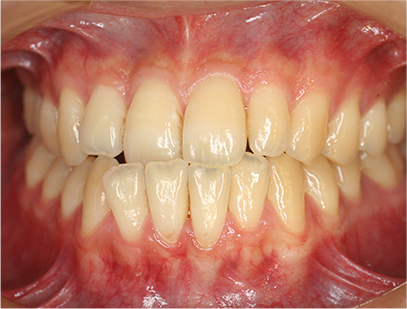

症例01|中学生の男子

前歯部の反対咬合

前歯部の反対咬合と上顎前歯のデコボコを主訴として来院されました。精査、診断の結果「前歯部に叢生を伴う反対咬合」と診断されました。

治療計画

非抜歯にて前歯の再配列、反対咬合の改善を行う事にしました。

治療前

• 正面

治療後

治療前の写真と比べると前歯部の反対咬合は改善されて、上顎の前歯部のデコボコも綺麗に並べる事ができました。

また口元は上の歯が前に出たために口唇がへこんでいたことも改善されて男らしい綺麗な口元に改善できました。 治療期間は2年と6か月を必要としました。